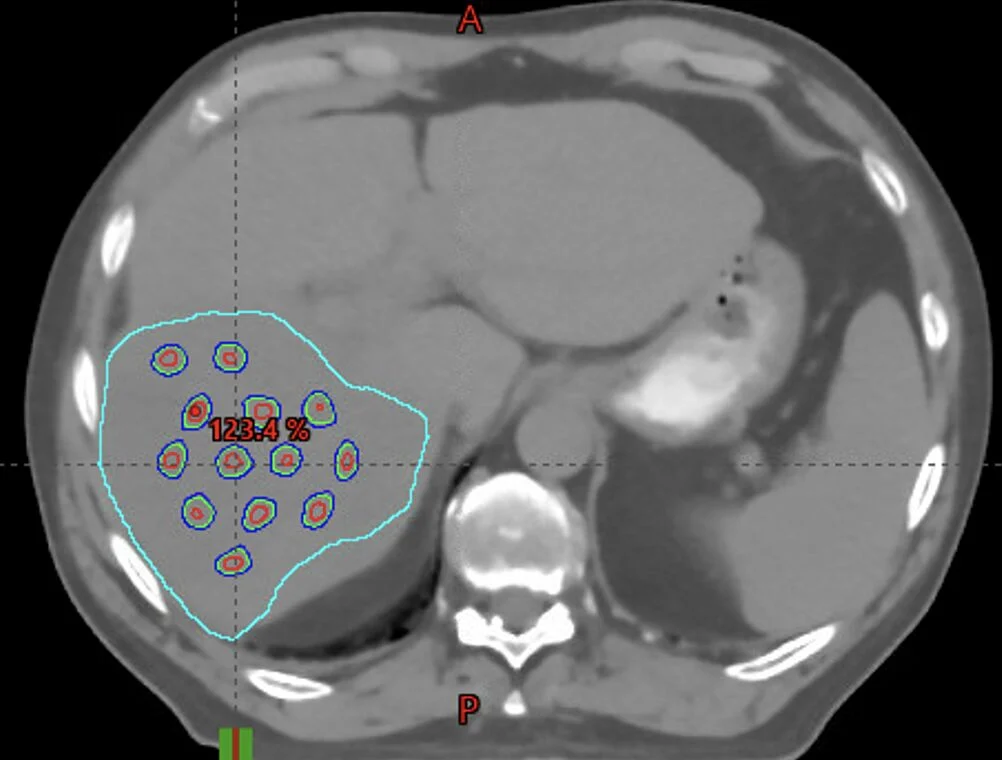

Instead of treating the whole tumor, you just treat a dot pattern through the tumor. It seems high-dose radiation in a dot pattern can be very effective and has less side effects. This approach may be especially relevant for tumors that are very large.

We are conducting a clinical trial The University of Kansas Cancer Center combining Grid Radiation Therapy with immunotherapy, and we’ve seen some dramatic tumor responses!